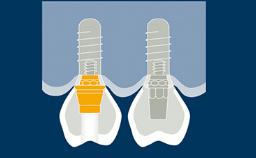

Quando os implantes são instalados e restaurados com as próteses finais, alguns princípios devem ser seguidos para obter um bom ajuste e sucesso a longo prazo da prótese. Os princípios gerais para a entrega de uma prótese implantossuportada são muito semelhantes àqueles para a entrega de uma prótese suportada por dente. No entanto, a complexidade é maior quando se utilizam próteses implantossuportadas, uma vez que elas podem ter múltiplos componentes que se encaixam muito precisamente ao longo de caminhos limitados de inserção. Além disso, essas próteses precisam ser entregues em implantes rigidamente fixados. Todos esses fatores tornam isso um procedimento muito mais rigoroso. Portanto, é importante ter um protocolo para garantir que as etapas corretas sejam seguidas, a fim de minimizar o risco de complicações e de poder verificar se o procedimento foi realizado corretamente. Também é importante poder fornecer informações de linha de base sobre a prótese contra as quais você pode comparar a condição ao longo do tempo.

- descrever as técnicas clínicas para a montagem de próteses parafusadas e cimentadas